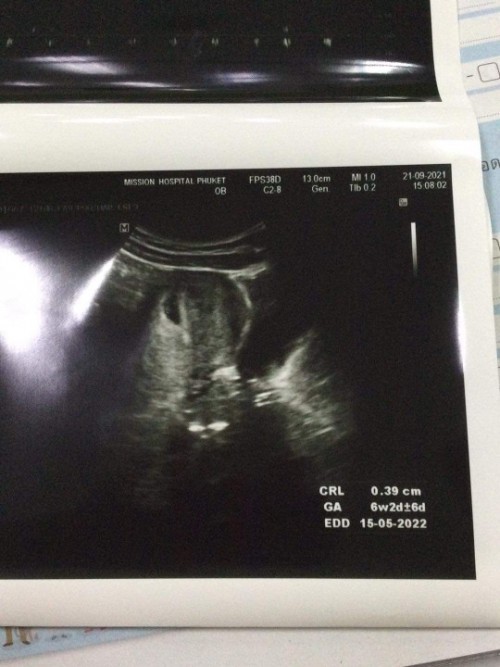

บ้านนี้ตรวจ 7W2D เจอตัว พร้อมหัวใจเต้นค่ะ